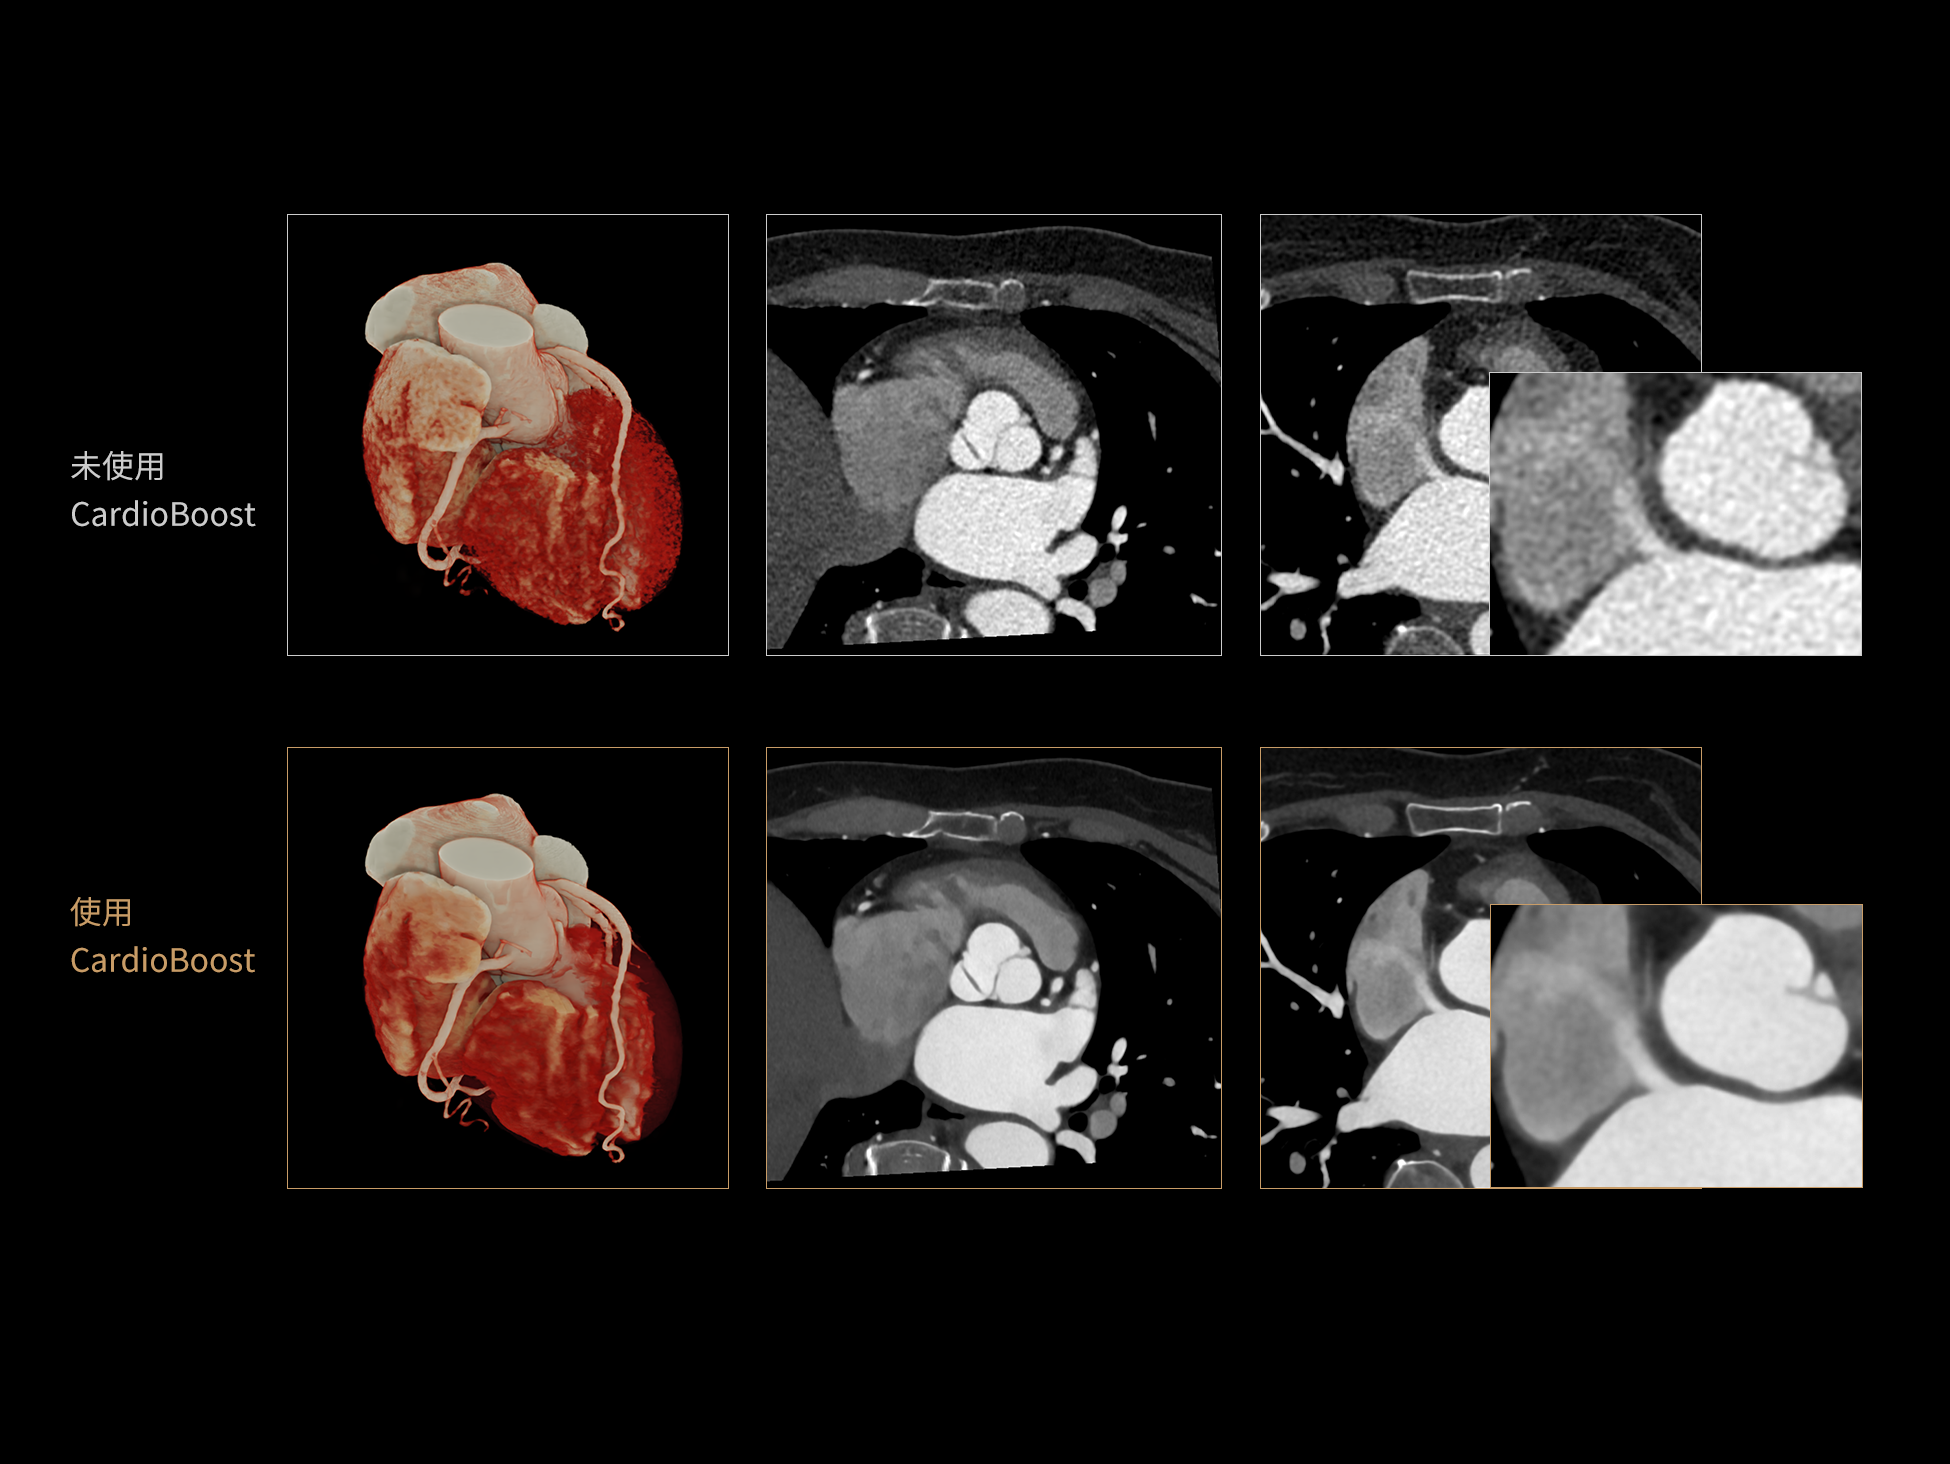

CardioBoost:专属网络设计,重塑心脏影像表现

uCT 868 搭载联影最新一代 uSense 人工智能平台,将智能化深度融入 CT 扫描全流程,从感知细微生理运动到精细结构探测,再到多场景诊疗优化。以 AI 为核心驱动力,uSense 重塑成像各环节,打造高效、高清的智慧扫查体验。在心脏成像领域,uSense 结合宽体探测器、心脏专研AI重建算法与AI冠脉运动追焦技术,在保持低剂量的同时,有效抑制运动伪影,精准呈现软斑块、混合型斑块及支架细节,助力冠脉成像惠及更多患者。针对多科室疾病临床应用场景,uSense 平台提供全方位的智能解决方案:包括头部运动伪影智能校正、金属植入物伪影抑制、扫描视野扩展等先进算法。这些创新技术使 uCT 868 能够构建覆盖全场景的智能诊疗体系,持续拓展 AI 赋能医学影像的边界。

作为高端CT解决方案平台,uCT 868 凭借高速扫描能力、宽体探测器、AI驱动重建算法和智能工作流,能够从容应对上述急症场景下的多部位、多模式联合检查需求。不论是冠脉、主动脉与肺动脉的一站式成像,还是卒中的快速识别,亦或是全身创伤评估中的快速定位与精细结构显示,uCT 868 均能以高速、清晰、低剂量的成像表现,助力临床在关键时刻做出快速而准确的诊断判断,赢得宝贵救治时间。